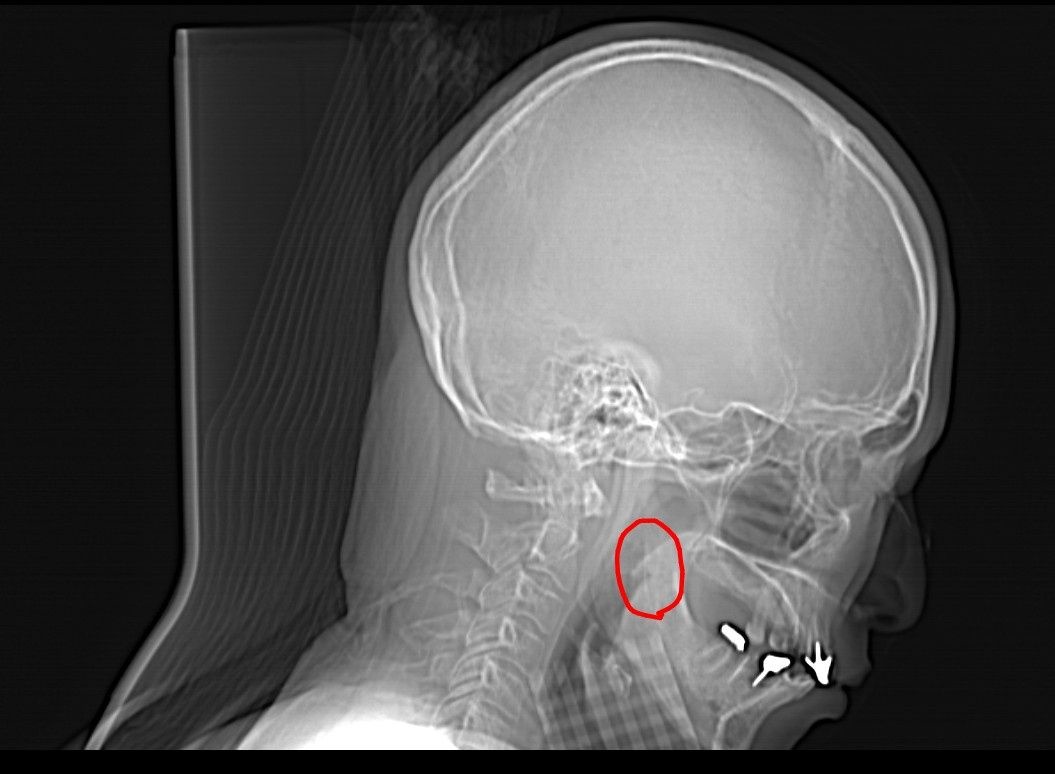

魚の骨(アジ)が刺さったんだけど医者に行っても見当たらない、CT撮ってもこれは魚の骨じゃないって言われるんだよ

でも10月に刺さってからずっとしゃべりにくいし食事も柔らかくしないと喉を通らないんだよ

常に喉をチクッと刺す感じ

有識者から診てどう見えるかな?

そうCTに写っている位置と痛みがある位置が感覚では一致してる

でもこんなところに魚の骨があるわけないって言われて取る形もしてもらえないんだ…

奥にズズッと行く感覚があるから

おそらく最初は外から見えている位置にあったんだと思うけど見てもらう頃には粘膜に埋まってしまって見えなくなったんじゃないかと思う

今日も紹介状をもらった大病院でこの画像を見せたんだけど「魚の骨じゃないですね」って言われた

それで終わらせられそうになったからなんとか色んな断面で頭部を撮ってほしいってお願いしてなんとか撮ってもらえた

で結果を1週間後に2人の専門家に見てもらって結果を聞く